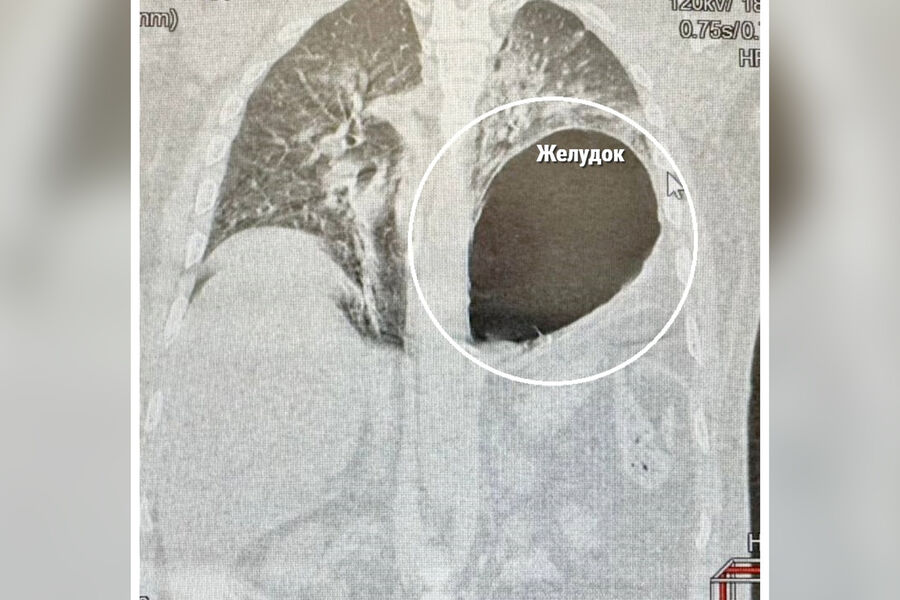

На момент поступления в медучреждение пациент с трудом двигался и дышал. Диагностика показала, что у него закрытая травма груди и живота, перелом нескольких ребер, разрыв диафрагмы со смещением желудка в плевральную полость.

«Левое легкое спалось, а желудок практически переместился в плевральную полость и сдавил сердце и средостение. Развился шок, и счет шел на минуты. Мы выполнили экстренную лапаротомию, низвели желудок, дренировали левую плевральную полость и ушили дефект диафрагмы», — рассказал хирург больницы Сергей Поликарпов.